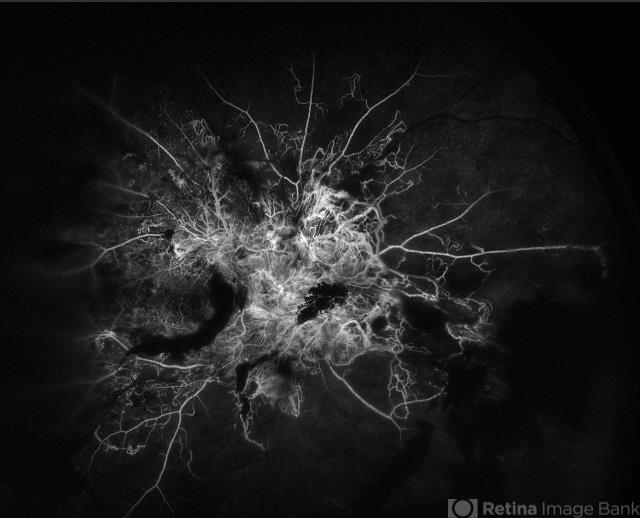

By Brandon I Fram, MD, BS

Retina and Vitreous of Texas - Uploaded on Oct 13, 2024.

- PDR, neovascularization of the disc (NVD), proliferative diabetic retinopathy (PDR), fluorescein angiogram (FA), florid type PDR

- 28 year-old with florid neovascularization of the disc and extensive nonperfusion imaged with fluorescein angiography